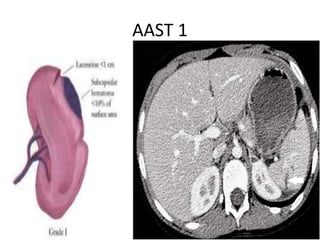

AAST Grading:

AAST 1